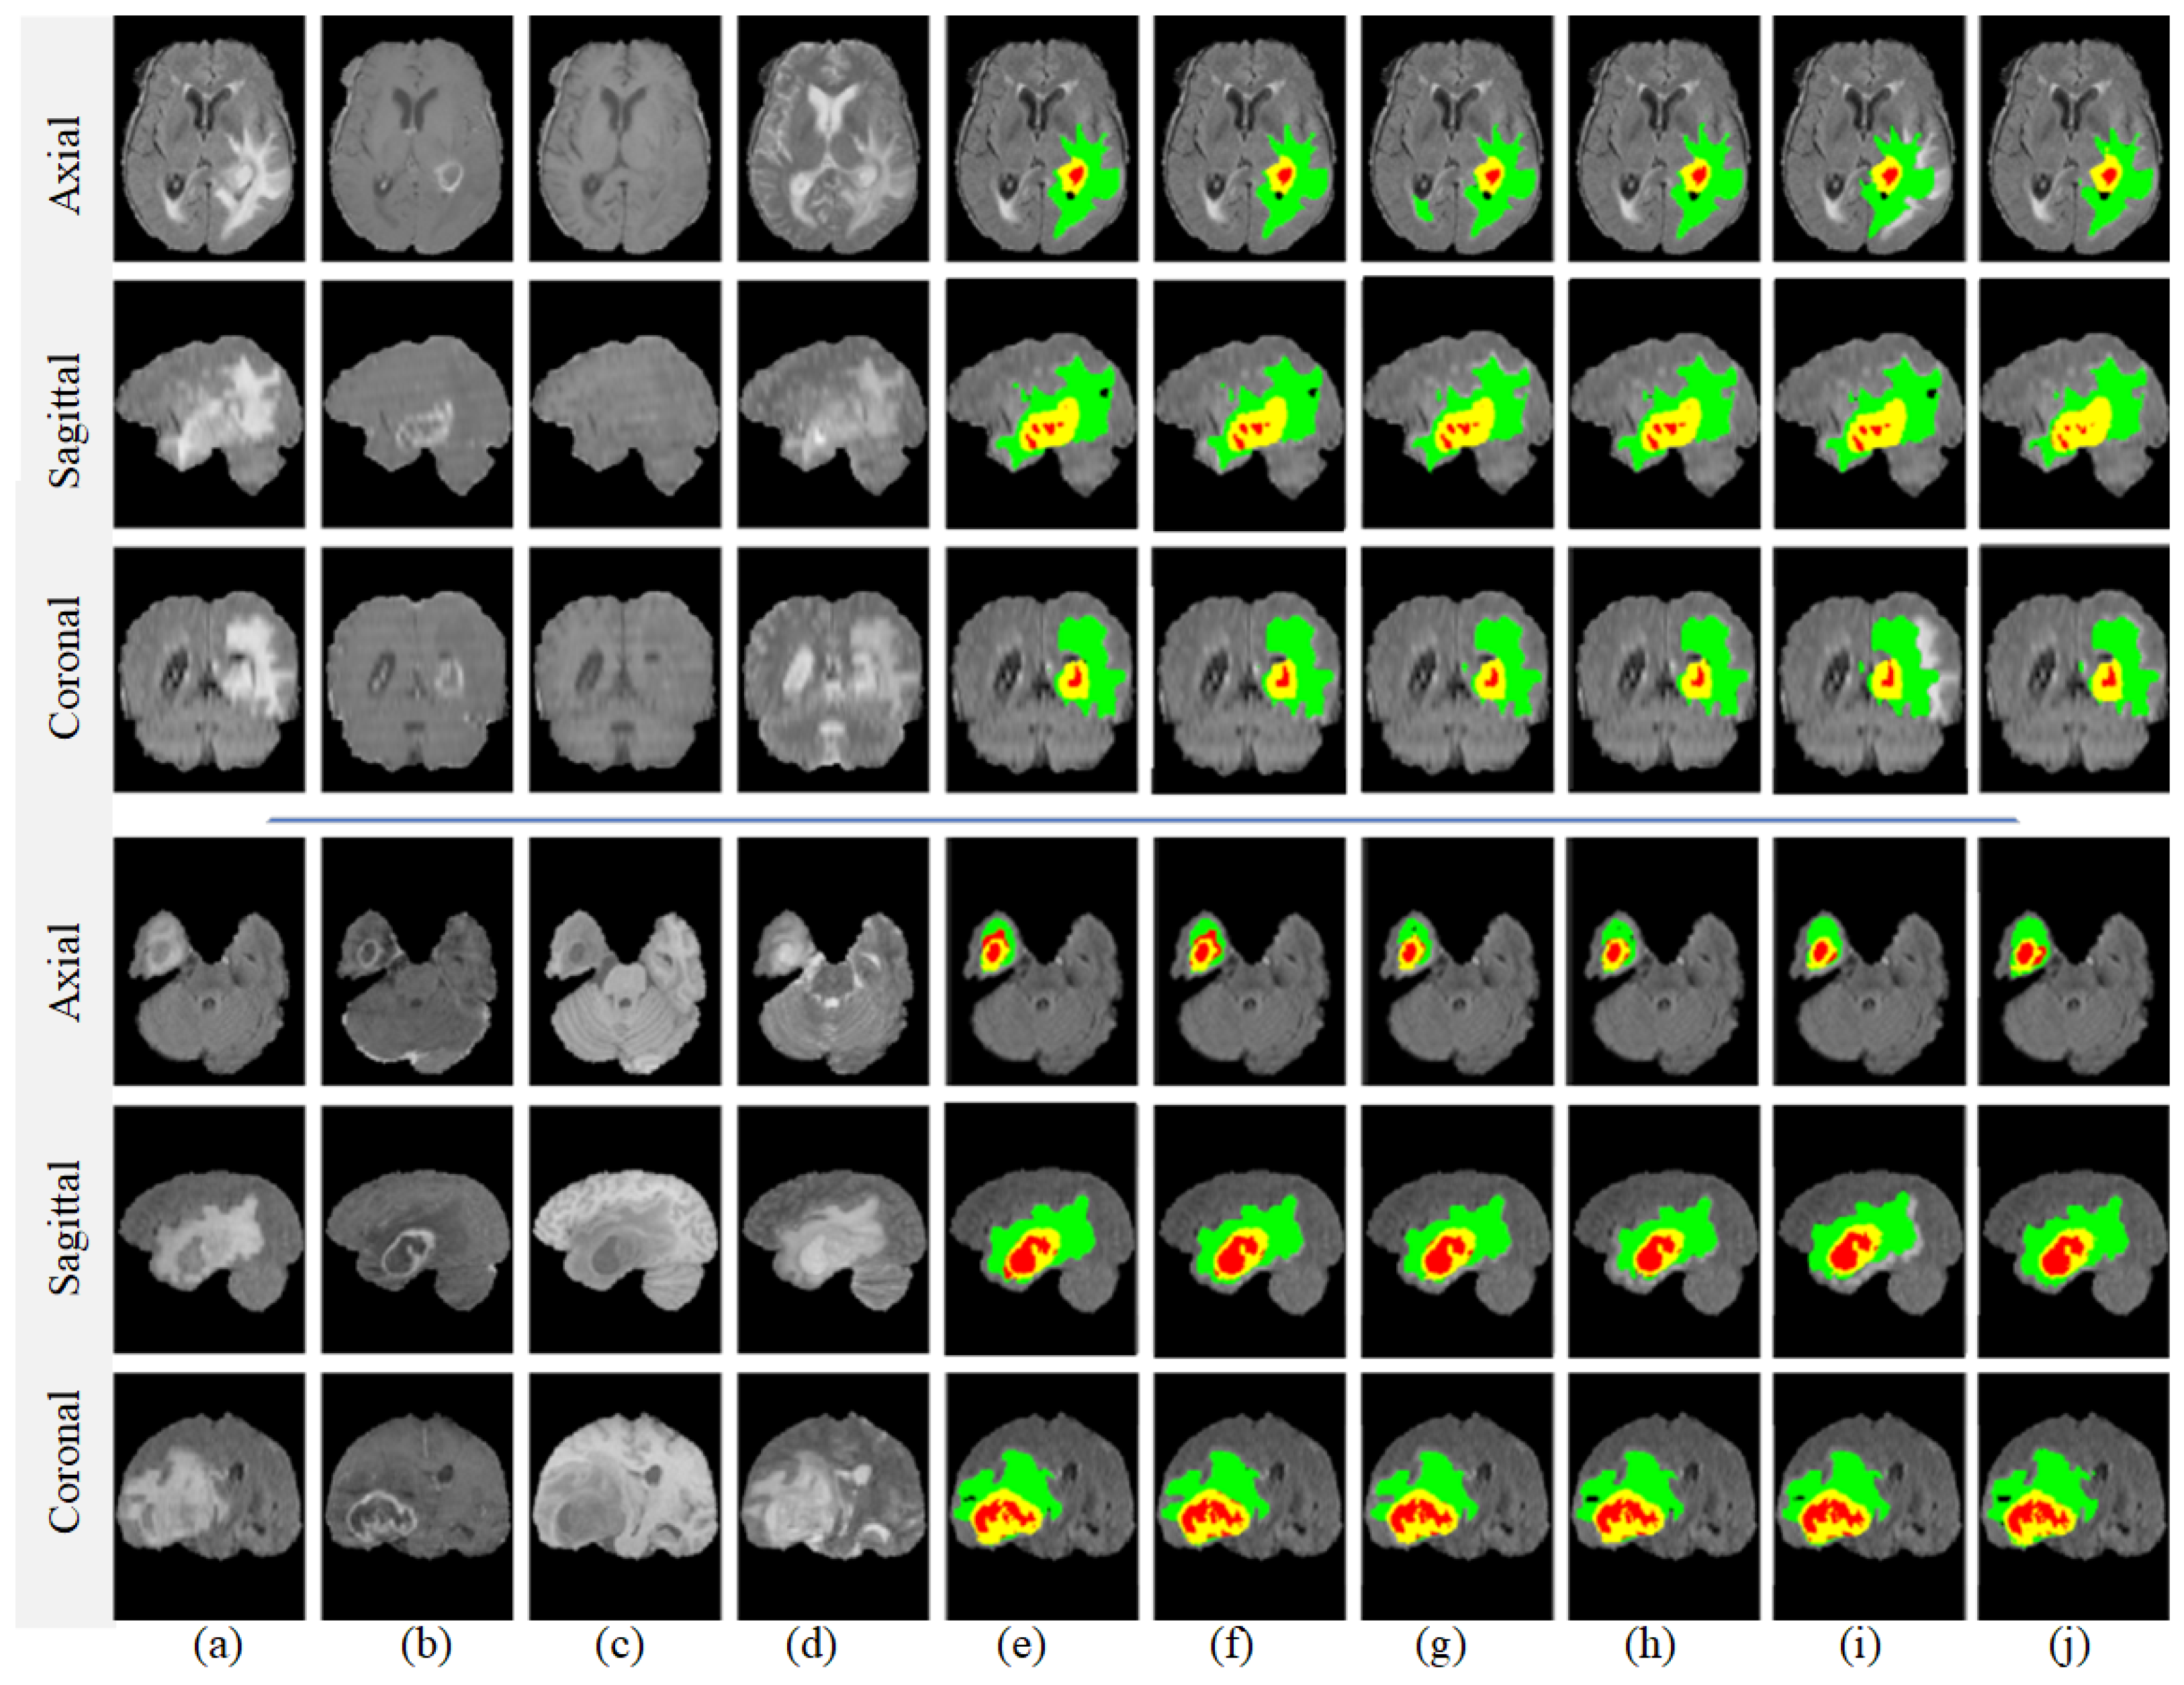

To conclusively demonstrate the high performance and effectiveness of our proposed model, we initially conducted a series of validation experiments. Notably, these experiments were performed with and without making comparisons with previous models. The images used for this purpose, displayed in Figure 9, were sourced from the BRATS2018 dataset. After applying our enhancement algorithm to these original images, we then proceeded to segment the brain tumors using our model. According to the visual results, it is evident that our proposed model yielded outcomes that closely align with the ground-truth data. However, the segmentation outcome in the final row closely approximates the ground-truth result. Overall, these findings further corroborate the robustness and accuracy of our model.

Figure 9.

Segmentation results for brain tumors using our proposed model. (a) FLAIR, (b) T1, (c) T1ce, (d) T2, (e) our obtained results, and (f) ground truth. The colors in the segmentation images signify different conditions: green represents edema; yellow indicates an enhancing tumor; and red denotes both necrosis and non-enhancing regions.

Furthermore, we conducted another experiment to validate our proposed model’s performance and compare it with previous approaches. The segmentation outcomes are illustrated in Figure 10, which highlights the advantages of the method proposed in this paper. Notably, our approach yielded smoother segmentation along the edges of the tumor. A detailed examination of the images in rows 1 and 2 further revealed that existing methods such as HMNet [55] and TransConver [44] struggled with over-segmentation in the core tumor regions when compared with ground-truth images. Specifically, as shown in row 3, both HMNet [55] and TransConver [44] erroneously categorized pixels located above the core tumor area as belonging to the tumor itself. This is a significant point of differentiation: our proposed method more accurately segments the core tumor area, aligning more closely with the ground-truth image. Overall, these findings bolster the case for the effectiveness and precision of our segmentation method.

Figure 10.

Comparison of segmentation results attained by proposed model and previous models. (a,f) Input image, (b,g) HMNet [55], (c,h) TransConver [44], (d,i) ours, and (e,j) ground truth.